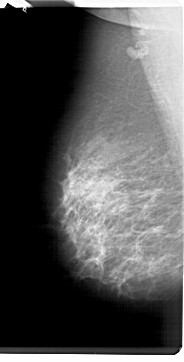

A_1298_1.LEFT_MLO

LEFT_MLO LINES 6871 PIXELS_PER_LINE 3481 BITS_PER_PIXEL 12 RESOLUTION 43.5 NON_OVERLAY